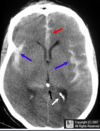

What type of hameotoma is depicted? Epidural haematoma (EDH) Subdural haematoma (SDH) **Subarachnoid haematoma (SAH)** Intracerebral haematoma (ICH) There is high-attenuation blood in the Sylvian fissures (blue arrows) and the interhemispheric fissure (red arrow) seen on this non-contrast enhanced CT of the brain. Do not confuse normal, physiologic calcifications (white and black arrows) for bloo